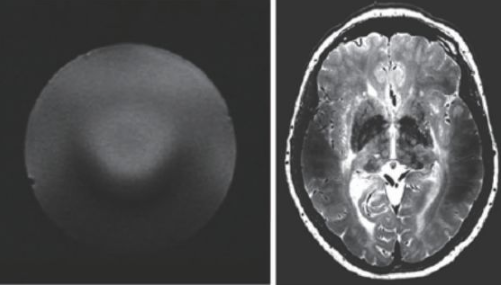

因此,磁共振成像技術(shù)目前的發(fā)展趨勢(shì),是朝著更高磁場(chǎng)強(qiáng)度發(fā)展,以期獲得更高分辨率的圖像,并實(shí)現(xiàn)多核成像。圖6 顯示了磁場(chǎng)強(qiáng)度的高低對(duì)圖像分辨率的影像,(a)為7 T 磁場(chǎng)下的圖像,(b)為0.35 T磁場(chǎng)下的圖像,二者的圖像分辨率可見一斑。

image.png

圖6 T2 加權(quán)成像(a)7 T 下的成像,分辨率約0.3 mm;(b)0.35 T下的成像,分辨率約1 mm